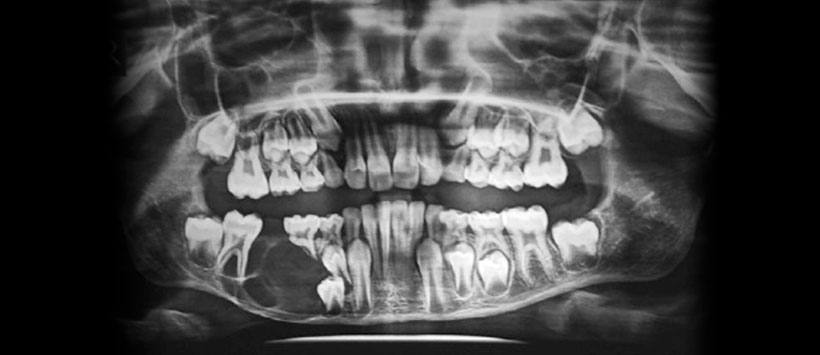

Figura 2: Radiografía panorámica de un paciente pediátrico en el que se visualiza una lesión osteolítica agresiva en el cuarto cuadrante que ocasiona desplazamiento de piezas dentarias, del conducto dentario inferior, adelgazamiento del reborde basal mandibular y reabsorción radicular